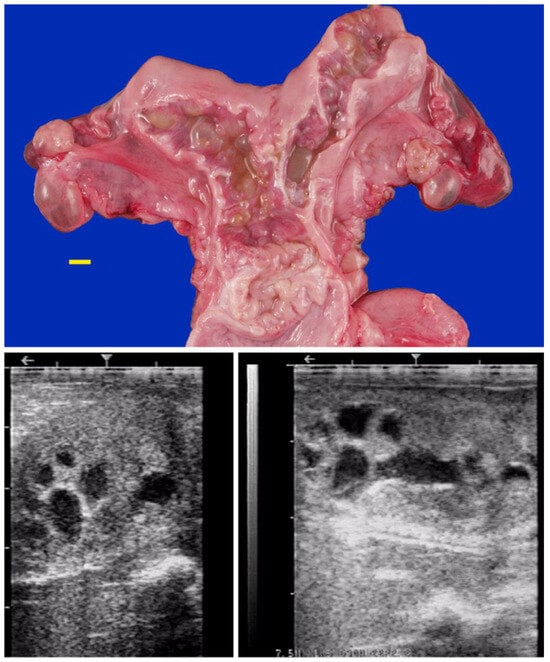

Pyometra and non-congenital mucometra are often due to cervical or vaginal adhesions resulting from poor handling of dystocia or fetotomy [7,14,63]. Uterine cysts and intraluminal adhesions have also been observed following dystocia or postpartum uterine prolapse (Figure 13).

Figure 13. Gross pathology (scale bar: 1 cm) and ultrasonogram of intraluminal uterine cysts due to intraluminal uterine adhesions in an alpaca.